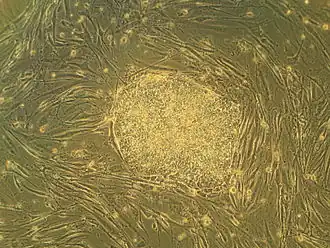

Human embryonic stem cells in cell culturePluripotent: Embryonic stem cells are able to develop into any type of cell, excepting those of the placenta. Only embryonic stem cells of the morula are totipotent: able to develop into any type of cell, including those of the placenta.

Embryonic stem cells (ESCs), derived from the blastocyst stage of early mammalian embryos, are distinguished by their ability to differentiate into any embryonic cell type and by their ability to self-renew. It is these traits that makes them valuable in the scientific and medical fields. ESCs have a normal karyotype, maintain high telomerase activity, and exhibit remarkable long-term proliferative potential.[6]

Embryonic stem cells of the inner cell mass are pluripotent, meaning they are able to differentiate to generate primitive ectoderm, which ultimately differentiates during gastrulation into all derivatives of the three primary germ layers: ectoderm, endoderm, and mesoderm. These germ layers generate each of the more than 220 cell types in the adult human body. When provided with the appropriate signals, ESCs initially form precursor cells that in subsequently differentiate into the desired cell types. Pluripotency distinguishes embryonic stem cells from adult stem cells, which are multipotent and can only produce a limited number of cell types.